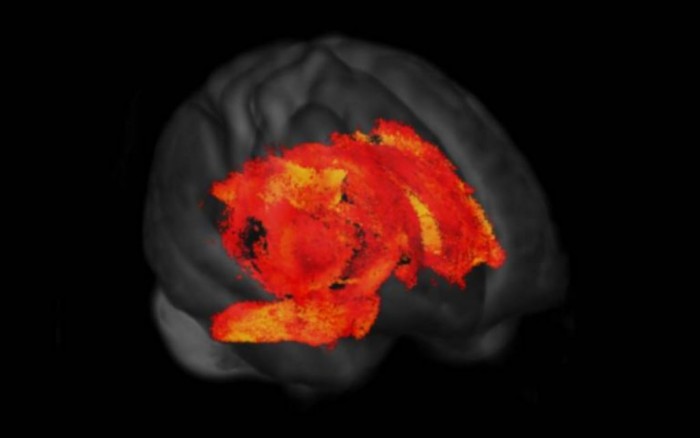

第二篇论文这是采用静息状态功能MRI(rsfMRI)和弥散加权成像,仔细观察帕金森病患者大脑中的结构和功能连接如何恶化,以及如何与视觉功能障碍和痴呆症相关联。

第二篇论文的研究人员表示:“我们的研究结果表明,PD中整个皮层的结构-功能连接耦合被严重破坏,在低视觉表现者(他们有较高的痴呆风险)的颞叶结构中甚至有更明显的脱钩。表明,PD中的结构-功能连接解耦遵循同样的宏观组织原则,这些原则指导着健康个体的SC-FC[结构-功能]耦合,但解耦速度加快”。